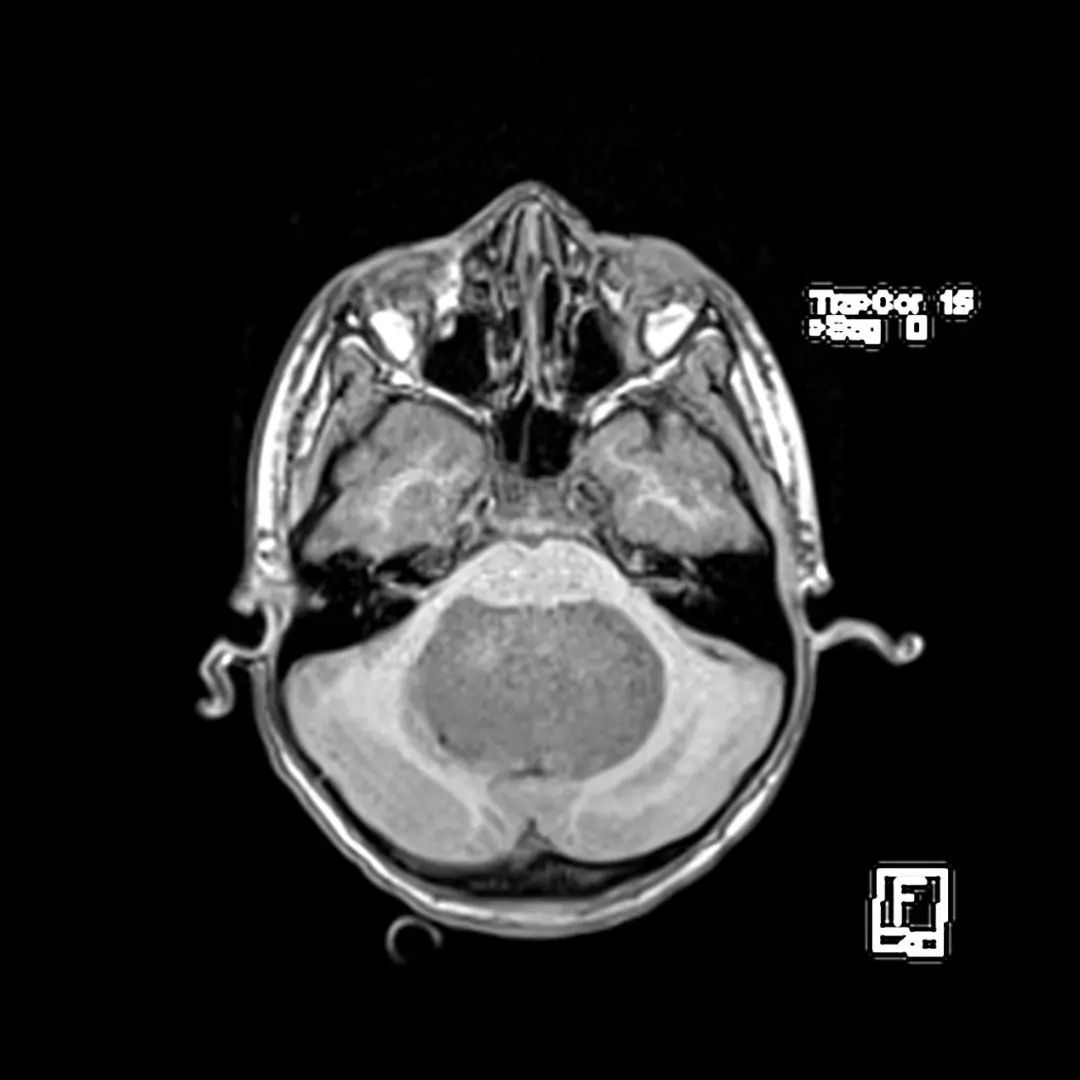

CT表现

- 病灶形态:圆形/卵圆形,边界清楚。

- 密度:多数略高,可见轻度瘤周水肿。

- 效应:儿童引起占位效应,可合并阻塞性脑积水。

- 增强后:均匀强化,囊变、坏死则不均匀强化。

中线小脑肿块,充满第四脑室并压迫脑干和小脑。与周围正常小脑相比,肿瘤在T1 WI上呈低信号,在T2 WI上呈轻度高信号,不均匀强化,呈囊/坏死成分,弥散受限。病理髓母细胞瘤。